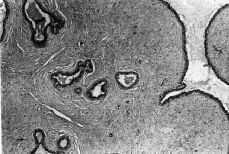

Figura 2.

Microscópicamente, los tumores sólidos se caracterizan por presentar un abundante tejido conectivo que artefacta la configuración lobular. El epitelio secretor expresa receptores para estrógenos y progesterona y se modifica bajo su influencia(12).